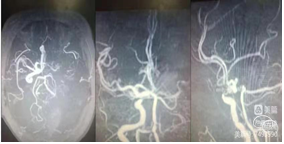

裸奔抽吸:通过导引导管将中间导管0.070-125cm置于颈内动脉起始部,"裸奔"边抽吸边上,抽吸3次,到达C4段,但以远血管仍不通畅。

导丝导引下抽吸:微导丝携带微导管,在中间导管支撑下到达C6-M1起始部,中间导管再次边抽吸边上至M1起始部,抽出部分血栓,中间导管造影示大脑前通畅,大脑中动脉仍不通。

支架取栓联合抽吸:再次将微导丝偿试通过M1段,到达大脑中动脉分叉部分,跟进微导管至分叉部,通过微导管释放4ⅹ20mm取栓支架,静置5分钟,向前跟进微导管,收拢支架,跟进中间导管至M1。边抽拉微导管和支架负压抽吸下将支架拉入中间导管内撤出体外,抽出大量黯红色血栓,支架内抓出黯黑色血栓。

中间导管内造影示大脑中动脉上干、下干通畅,远端血流良好,但上干、下干分叉后血管内仍有发白,考虑仍有血栓或斑块。

再次取栓:再次将支架置于M2段上干,释放支架,跟进中间导管至M1分叉近端,再次取栓和抽吸,取出少量血栓。

取出的大量血栓。